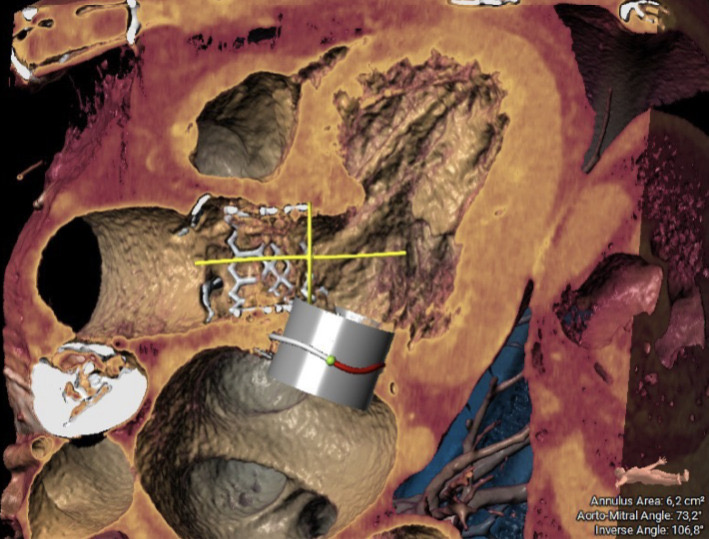

BACKGROUND Transcatheter mitral valve-in-valve implantation (TMVIV) into failing surgical bioprosthetic valves has evolved in recent years as a promising therapy to avoid redo cardiac surgery in patients at high surgical risk. METHODS An 80-year-old female patient with CKD stage 3, hypertension, a permanent PMK and atrial fibrillation was referred to our institution with NYHA Class III symptoms. She has undergone implantation of a bioprosthetic valve (St Jude Epic 29 mm) for severe mitral insufficiency due to chordal rupture in 2017 and transcatheter aortic valve implantation (Edwards 29 mm) for severe aortic insufficiency in 2022. The patient presented with structural valve degeneration, defined as intrinsic permanent variations of the tissue components of the valve, culminating in the development of severe intra-prosthetic stenosis. Notably her echocardiogram showed LVEF 45% with severe mitral valve deterioration due to calcification (mean gradient 15 mmHg, 3D MVA 0.8 cm^2). TAVI was normally functioning. Surgical risk for redo procedure was too high after evaluation by our Heart Team (EuroScore II 23,6%, STS Score operative mortality 16,7%). So, we have decided for a TMVIV using Edwards SAPIEN 3 Resilia valve 29 mm, implanted reversely in mitral position. The pre-procedural assessment for the "sizing" of the valve was performed using computed tomography angiography (CT). The following parameters were evaluated: the mitral annulus area, the aorto-mitral angle, the inverse angle and the distance between the two valves for evaluation of the neo-LVOT. The area of the mitral annulus was 6.2 cm² and thus suitable for a Sapien 3-29 mm. During procedure, angiographic imaging, but no TEE, suggested for a likely interference between the mitral valve balloon and the aortic frame, so we prepared for a simultaneous kissing balloon inflation between the mitral and aortic valves. RESULTS The post-procedural TEE showed no gradient, no obstruction in LVOT and no leak for either valves. CONCLUSIONS To our knowledge, we present a rare case of successful treatment utilizing simultaneous kissing balloon inflation during mitral valve replacement due to bioprosthesis degeneration, employing the Edwards SAPIEN 3 Ultra RESILIA valve. The case was characterized by challenges in visualizing the bioprosthetic valve ring as a reference point due to calcification.